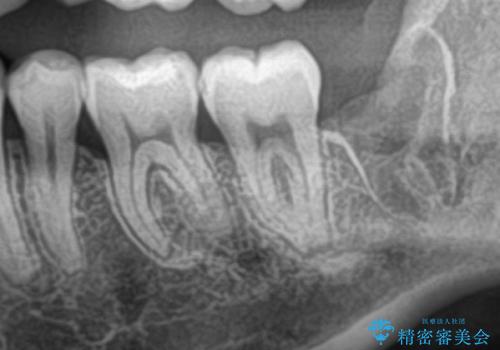

- 親知らずを抜きたいとのことで来院された患者様です。

CTで神経の位置などを確認し、抜歯術を行いました。

しっかり麻酔が効いたことを確認してから安全に抜歯を行いました。